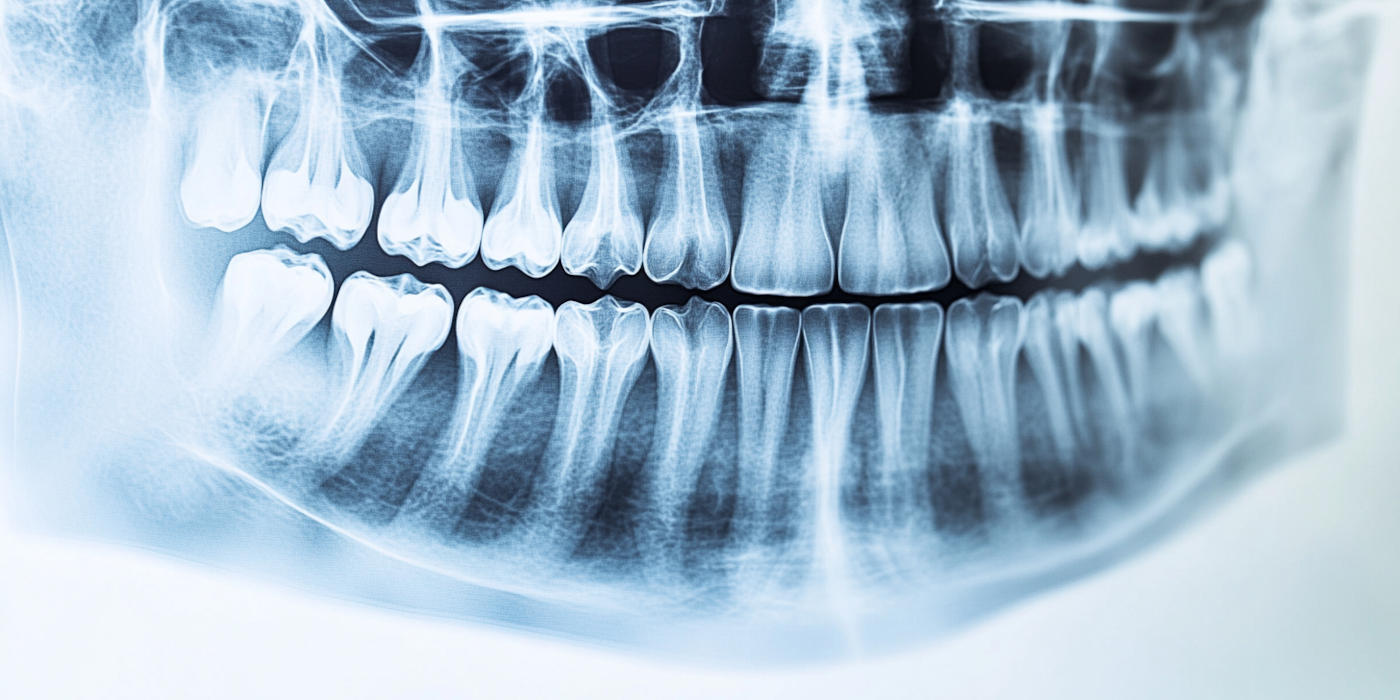

Implants dentaires Blanchiment dentaire Apnée du sommeil Facettes dentaires Les caries Traitement endodontique Prothèses dentaires Soin des gencives - Parodontie Dents de sagesse Urgence dentaire Hygiène bucco-dentaire Vidéos pédagogiques Vos dents à tout âge